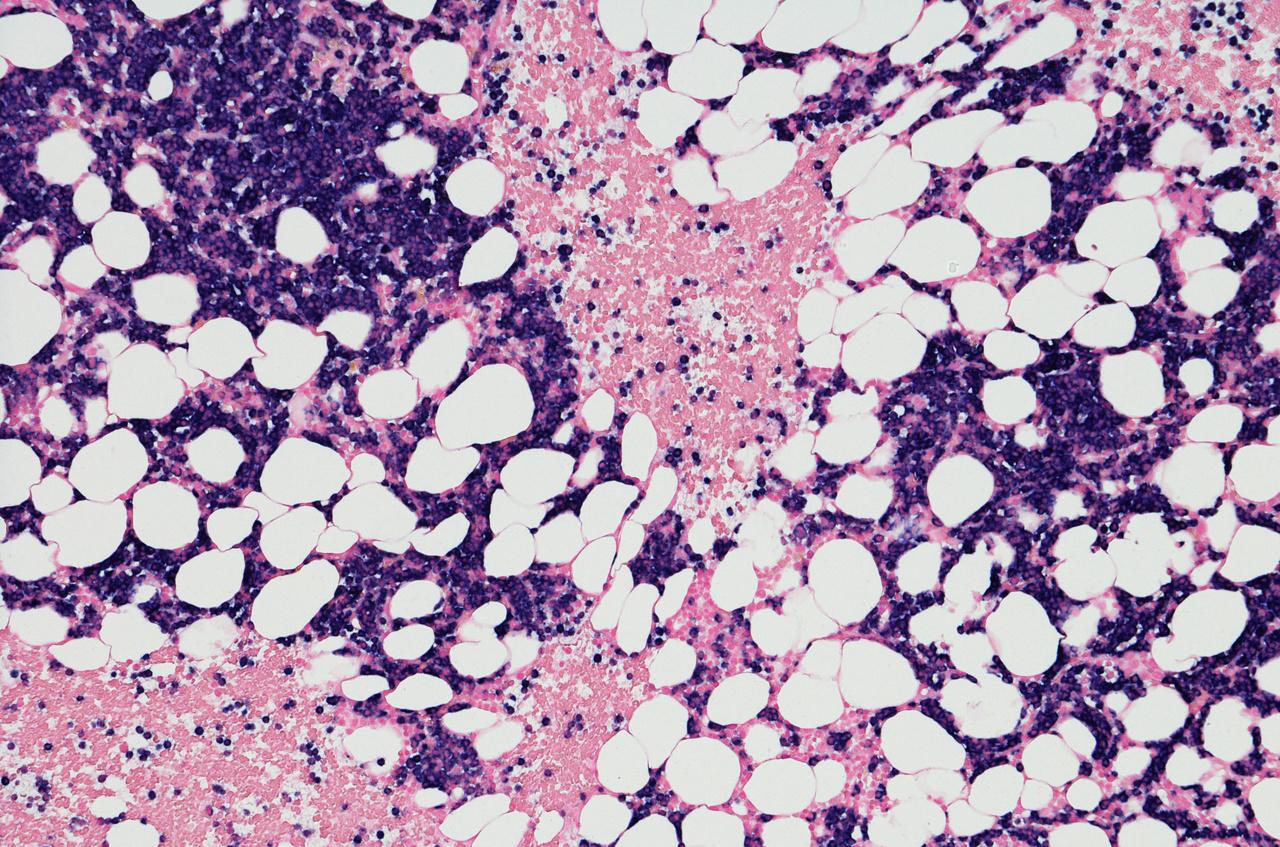

LEUKEMIA

Leukemia is a cancer of the body's blood-forming tissues, includingthebonemarrowandthelymphaticsystem.

Leukemiausuallyinvolveswhitebloodcells.Yourwhiteblood cells are potent infection fighters — they normally grow and divide in an orderly way, as your body needs them. But in people with leukemia, the bone marrow produces an excessiveamountofabnormalwhitebloodcells,whichdon't functionproperly.